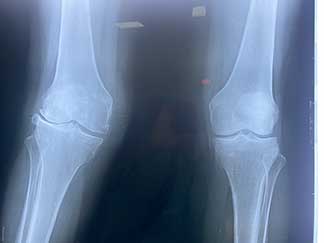

Prótesis de rodilla

También conocida como artroplastia de rodilla, es la sustitución artificial de la articulación desgastada por artrosis con un implante de metal y polietileno que ayuda a aliviar el dolor y restaurar la función.

¿Por qué se realiza?

La razón más frecuente es aliviar el dolor intenso causado por artrosis, corregir las deformidades angulares en varo, valgo y contractura en flexión en adultos mayores y para adultos jóvenes, está indicada en lesiones crónicas articulares que ocasionan un desgaste acelerado.